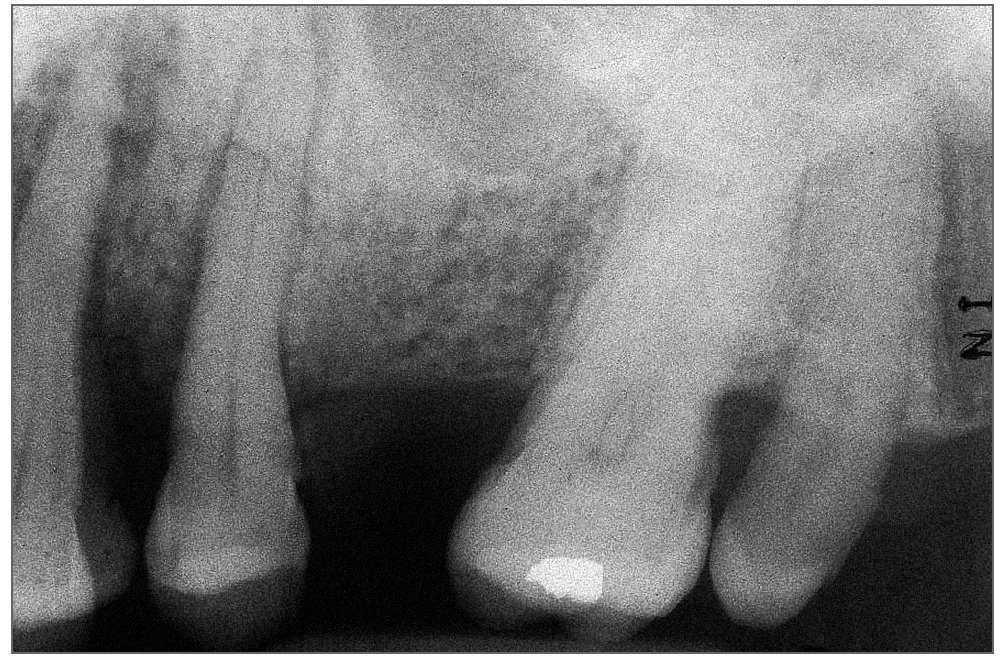

Se ordenó un estudio con tomografía computarizada de haz de cono (TCHC) para revelar la extensión completa de la lesión y visualizar la misma en relación con el resto de las estructuras del maxilar. La imagen reformada de la panorámica (fig. 4) reveló que la lesión quedaba comprendida en el interior de los alvéolos maxilares. El grueso de la lesión era una radiopacidad bien definida de forma irregular similar en aspecto al hueso. La opacidad estaba rodeada de un ribete radiolúcido. El hueso adyacente presentaba un aumento de densidad, extendiéndose más allá de la línea media de los alvéolos maxilares y mezclándose gradualmente con el patrón trabecular normal. En la zona posterior la hiperostosis se extendía a la región molar. Las proyecciones axial, coronal y oblicua (figs. 5 a 7) demostraron una perforación de la cortical vestibular y lingual de los alvéolos. Se advertía una posible perforación del suelo del seno maxilar izquierdo. Además, el seno maxilar izquierdo se encontraba significativamente velado por una opacidad con forma de cúpula.

Figura 5. Imagen de TCHC axial a nivel de la rama en la que puede observarse la perforación de las corticales vestibular y lingual del maxilar y el secuestro óseo dentro de la lesión.